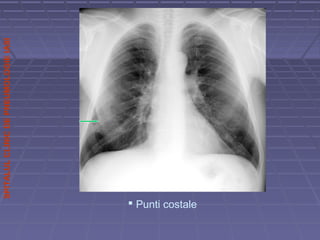

Schelet toracic:clavicule,omoplati coloanaSchelet toracic:clavicule,omoplati coloana ,,grilajgrilaj

 punti osoase anastomotice intre doua coastepunti osoase anastomotice intre doua coaste

 Punti costale